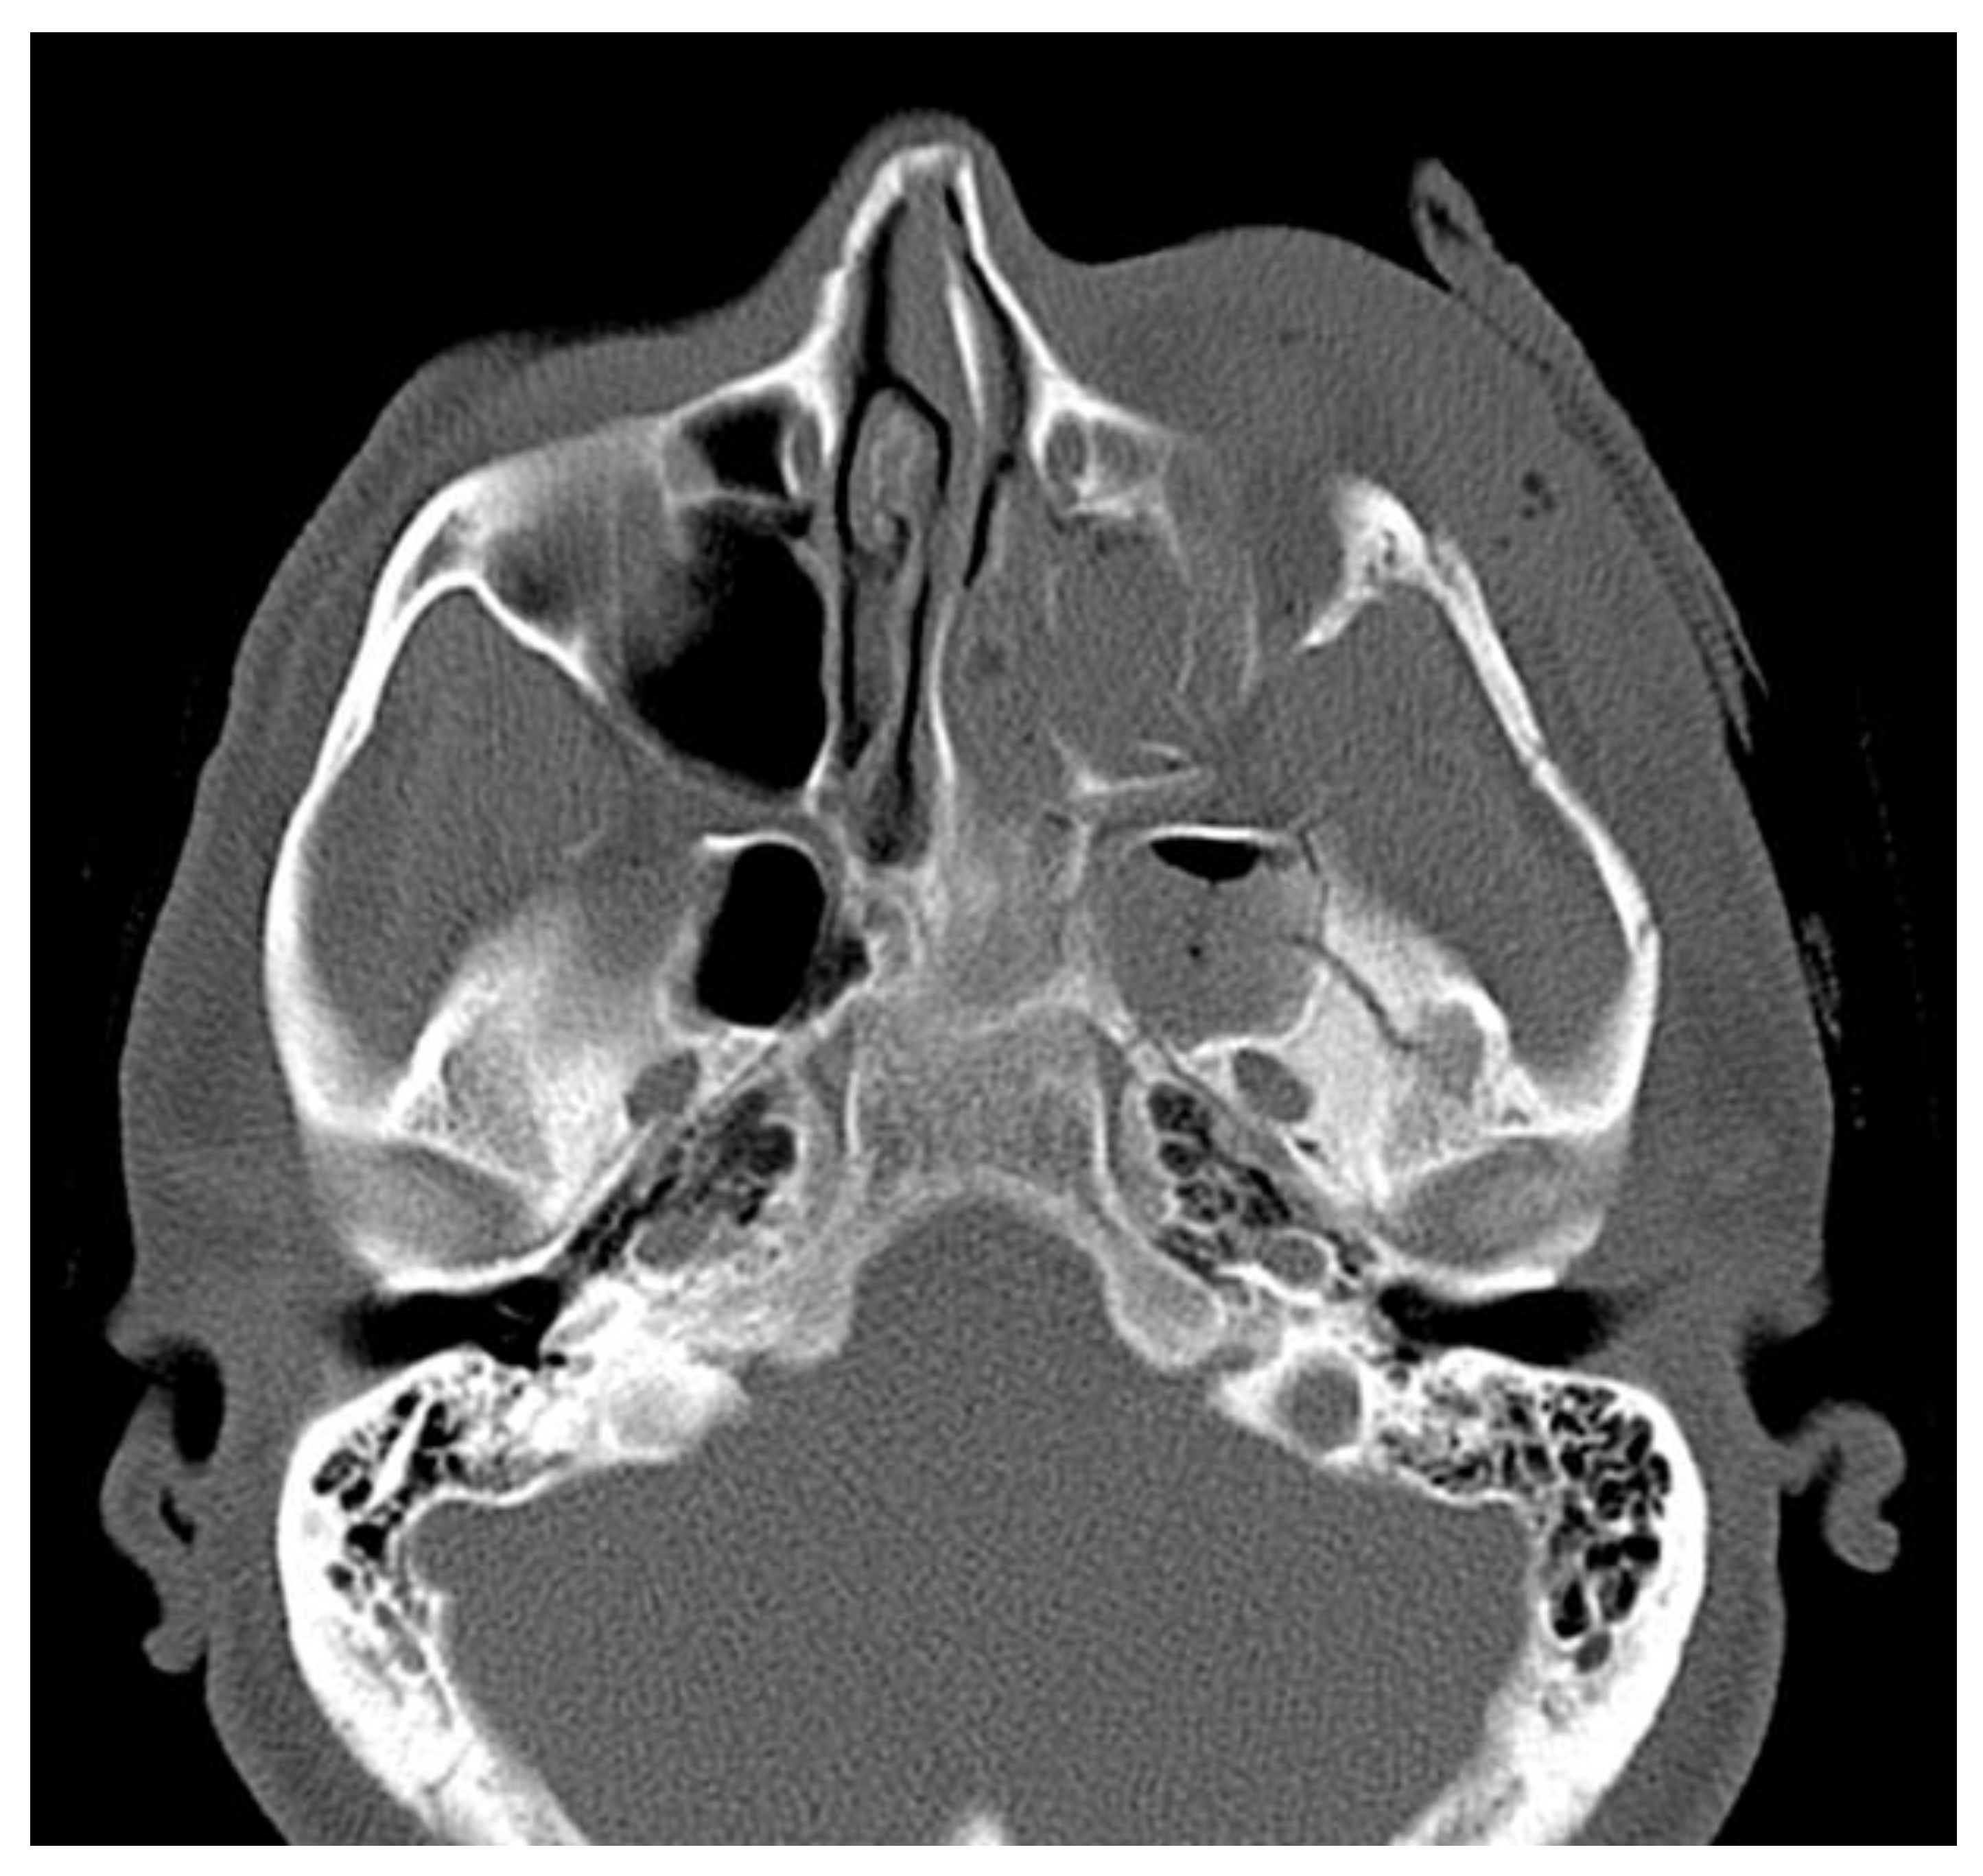

Figure 8. Trauma CT in axial view with visible orbital, zygomatico-malar fractures and displaced zygomatic arch.

Figure 9. Trauma CT in an axial scan with visible temporal bone fractures.